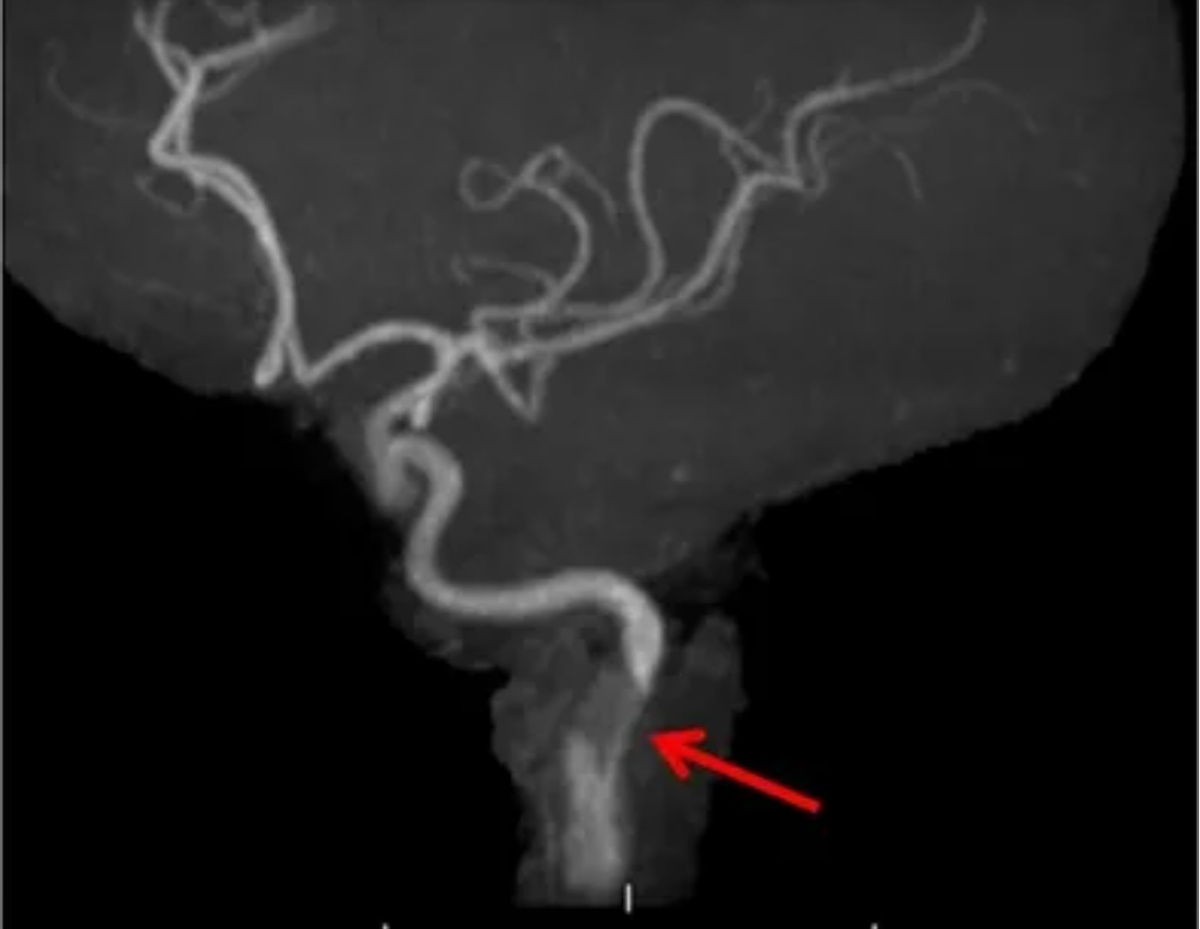

Через несколько часов его речь стала невнятной. Появилась слабость в правой руке и ноге. Испуганные родственники вызвали скорую. Врачи с подозрением на инсульт доставили его в сосудистый центр. Диагноз, который поставили после компьютерной ангиографии, звучал как диссекция позвоночной артерии.

Золотой стандарт диагностики диссекции позвоночной артерии- компьютерная томографическая ангиография. Метод позволяет визуализировать просвет сосуда, выявить сужение, окклюзию, наличие интрамуральной гематомы или отслоённой интимы. Магнитно-резонансная томография (МРТ) головного мозга необходима для оценки зоны ишемии- она покажет, пострадало ли вещество мозга от недостатка кровоснабжения .

В сложных случаях выполняется церебральная ангиография- инвазивное исследование с введением контраста непосредственно в сосудистое русло. Оно даёт максимально детальную картину состояния артерии, позволяет точно определить уровень и протяжённость диссекции, а при необходимости сразу перейти к эндоваскулярному вмешательству.